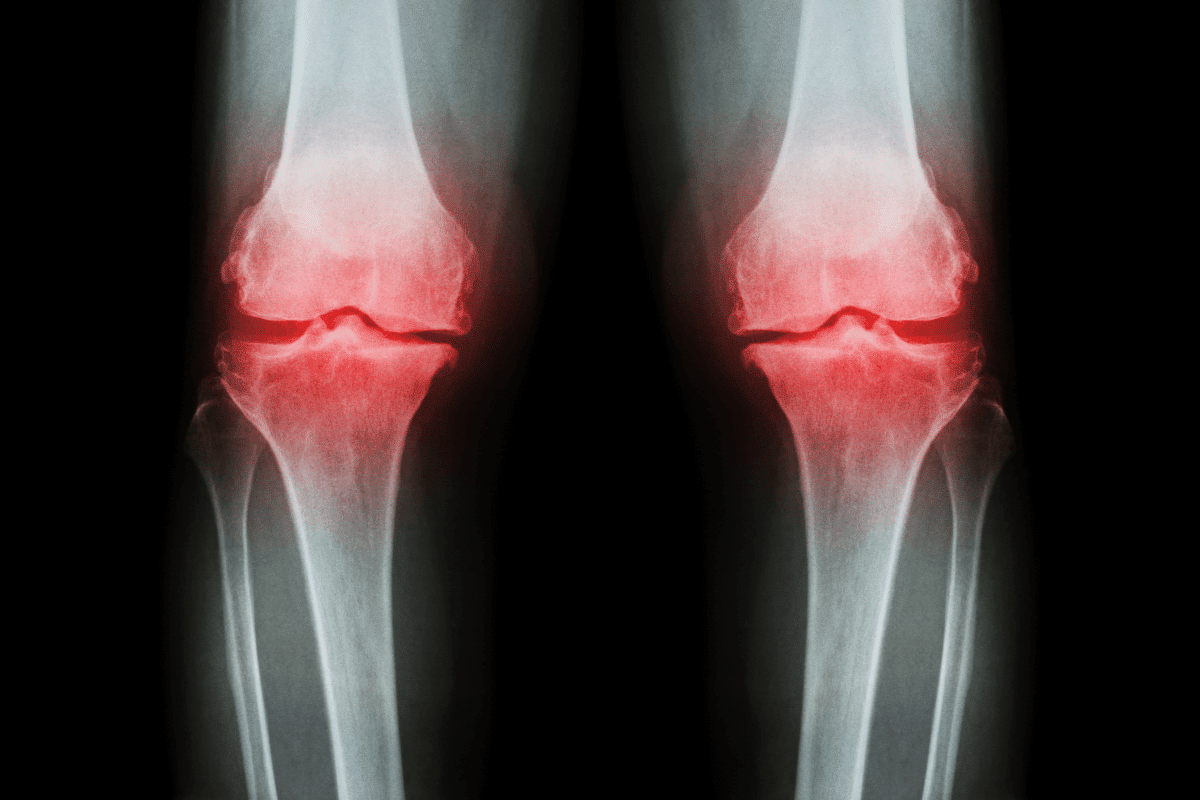

We know that RA is a chronic inflammatory disease. It causes pain, swelling, and inflammation in the joints. If not treated, it can lead to joint deformity.

Rheumatoid arthritis happens when the body’s immune system attacks healthy tissue in the joints. This leads to inflammation, pain, and stiffness. The exact reason for this is not fully known, but it’s thought to be a mix of genetics and environment.

RA affects more than just the joints. It can harm the heart and lungs, and cause fatigue and fever. These effects can greatly reduce a person’s quality of life.